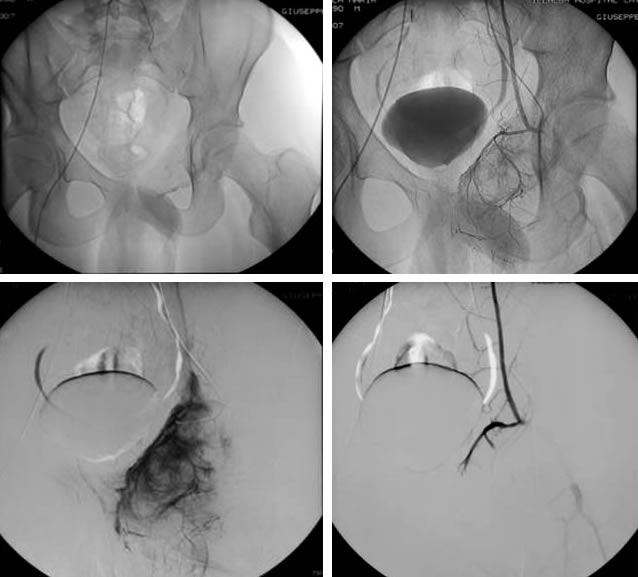

Le suddette lesioni presentano una ipervascolarizzazione patologica rifornita da uno o più vasi e sono caratterizzate dalla presenza di cavità incluse ripiene di detriti cellulari e sangue, separate da setti connettivali, sono tipici i livelli liquidi ben visibili alla TC ed alla RM.

L’embolizzazione arteriosa selettiva delle formazioni cistiche aneurismatiche, eseguita con l’utilizzo di GLUBRAN 2 (colla chirurgica) come mezzo embolizzante, blocca l’eccessivo apporto di sangue alla lesione, favorendone la guarigione. Ne consegue una ristrutturazione ossea che può essere parziale, sub-totale o totale del segmento interessato.

Adolescente di 16 anni.